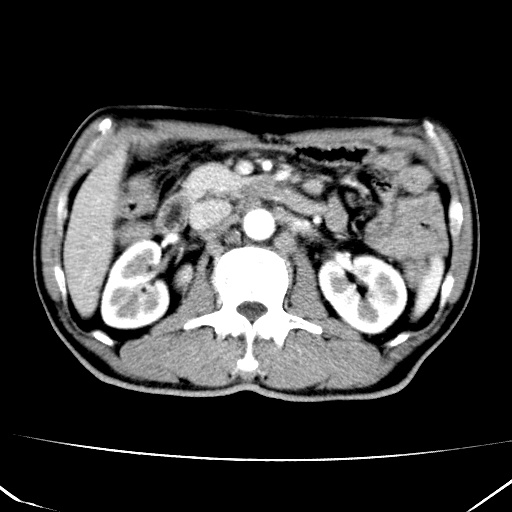

标题: CT17975:请求会诊。男、57岁。上腹部胀痛2天。临床诊断:糜 [打印本页]

标题: CT17975:请求会诊。男、57岁。上腹部胀痛2天。临床诊断:糜

肝脏多发类圆形低密度影,考虑肝脏转移瘤,肝胃韧带一淋巴结肿大,原发?胃癌?

考虑胃癌并肝脏及腹膜后淋巴结转移;不排除淋巴瘤。

肝内转移瘤,腹腔及腹膜后淋巴结转移。